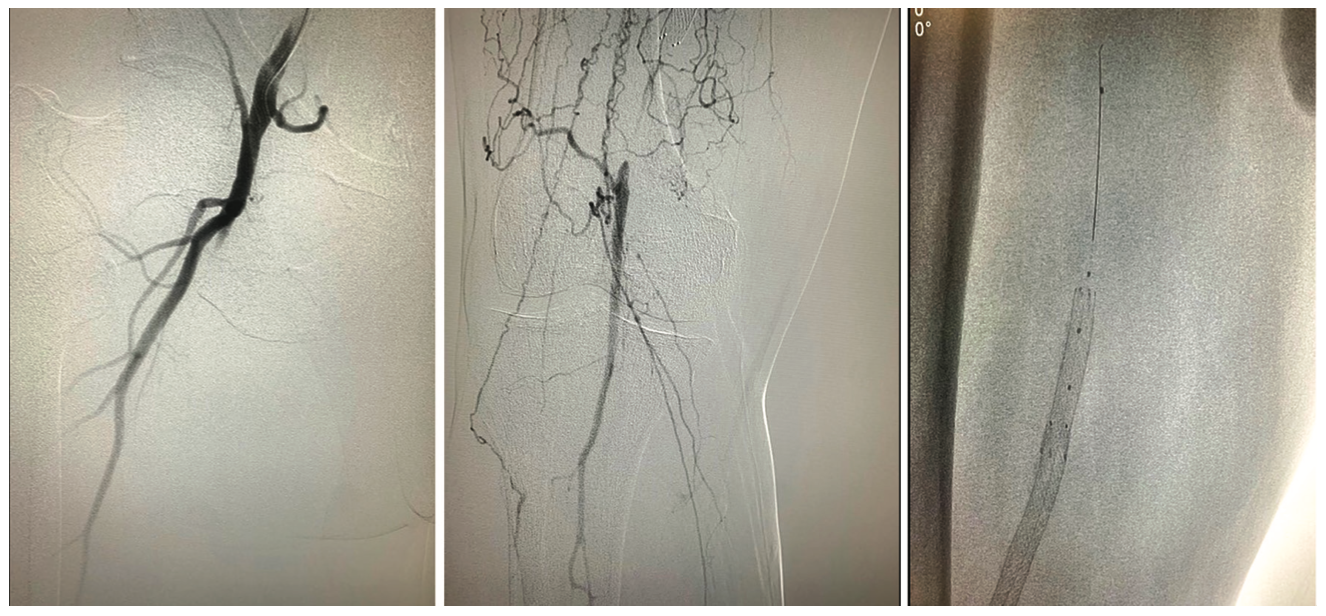

The left groin was accessed under ultrasound guidance, and a selective right lower-extremity angiogram revealed a patent profunda and proximal superficial femoral artery (SFA) occlusion with distal reconstitution (Figure 1) just distal to overlapping stents. There was a large posterior tibial artery providing single-vessel runoff.

Following the angiogram, a 6 French (Fr), 45 cm sheath was inserted. An antegrade .035-inch Glidewire (Terumo) was advanced with a microcatheter to keep the knuckle small. The wire was able to enter the stent in what appeared to be a luminal fashion, but at the overlap of the two stents, the wire would prolapse behind the overlap. Stiff penetrative wires were utilized in an effort to redirect (Halberd 12 gm and Astato 30 gm [both from Asahi Intecc]). This attempt proved unsuccessful, as there continued to be prolapse between the stent overlap. After some effort, the foot was accessed with ultrasound in the posterior tibial with a 4 Fr sheath (Figure 1). A retrograde intermediate tip polymer-jacketed wire (.018-inch Gladius [Asahi Intecc]) was able to get retrograde through the stent. The antegrade-retrograde knuckles appeared to overlap and the plans was for a reverse CART. In the process of advancing an .035-inch Charger balloon (Boston Scientific) from above, the antegrade knuckle advanced and collapsed by the retrograde. A directional stiff wire (.018-inch Halberd) was able to retrograde wire into the antegrade system. The retrograde .018-inch microcatheter was advanced into the contralateral sheath. Instead of externalizing the wire, a tip in was performed (Figure 2, Video 1).